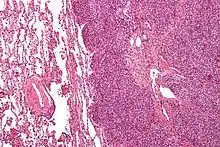

| Micrograph of metastatic Ewing sarcoma (right of image) in normal lung (left of image). PAS stain. | |

Ewing sarcoma is a small-blue-round-cell tumor that typically has a clear cytoplasm on H&E staining, due to glycogen. The presence of the glycogen can be demonstrated with positive PAS staining and negative PAS diastase staining. The characteristic immunostain is CD99, which diffusely marks the cell membrane. However, as CD99 is not specific for Ewing sarcoma, several auxiliary immunohistochemical markers can be employed to support the histological diagnosis.[23] Morphologic and immunohistochemical findings are corroborated with an associated chromosomal translocation, of which several occur. The most common translocation, present in about 90% of Ewing sarcoma cases, is t(11;22)(q24;q12),[24][25] which generates an aberrant transcription factor through fusion of the EWSR1 gene with the FLI1 gene.[26]